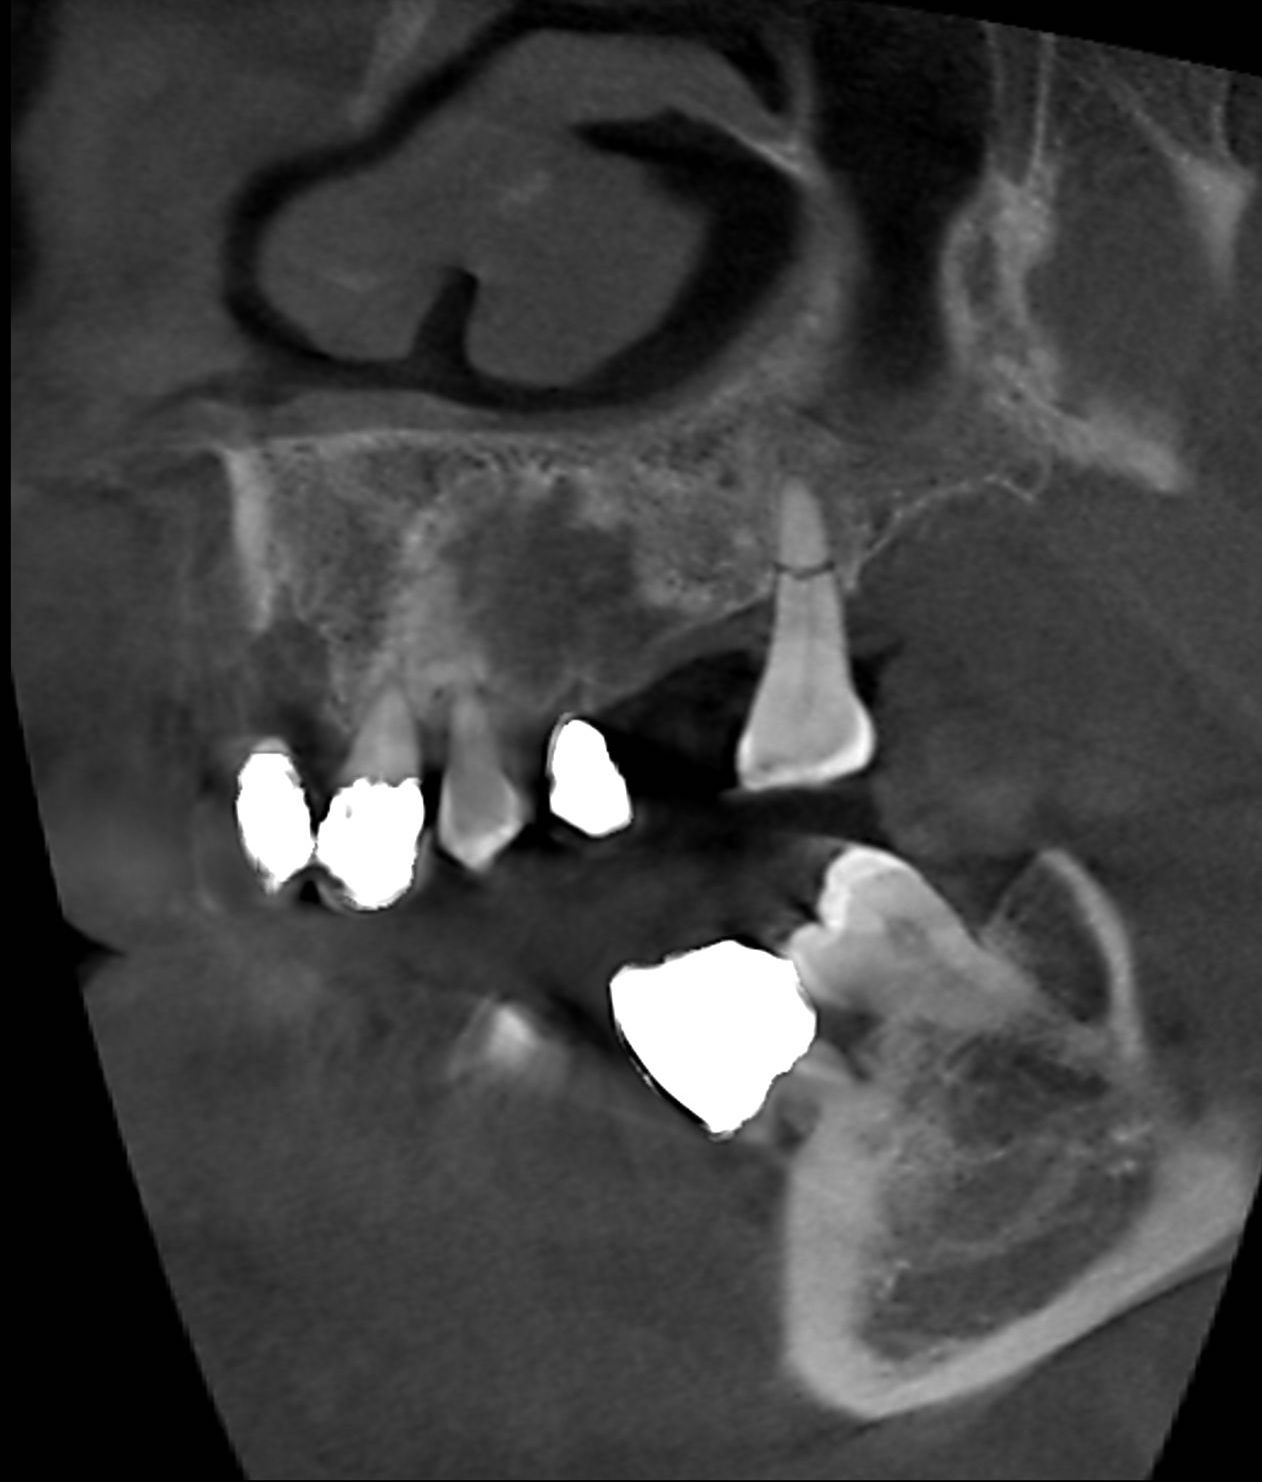

Le cone beam utilisé en pathologie dentaire et maxillo-faciale est indiqué pour l’examen des tissus minéralisés (dents, cartilages, os), il permet d’identifier les lésions osseuses, les fractures, les infections, les kystes ou les corps étrangers.

Le cone beam dentaire est par exemple indiqué dans les pathologies suivantes :

- pathologies infectieuses

- pathologies du parodonte

Ostéonécrose de la mandibule

- pathologies osseuses des maxillaires

- pathologie des ATM (articulations temporo-mandibulaires)

- kystes radiculaires

- pathologie des sinus maxillaires

- pathologies tumorales

- dents incluses, surnuméraires

- implants dentaires

SCANNER DENTAIRE (DENTALSCANNER)

Les nouvelles générations de scanner permettent de faire une acquisition d’un volume global d’une partie du corps et de travailler à l’intérieur de ce volume en isolant une structure anatomique donnée et de l’explorer dans tous les plans de l’espace.

Grace à la technique de seuillage il est possible de dissocier progressivement les dents des structures osseuses environnantes dans le volume donné.